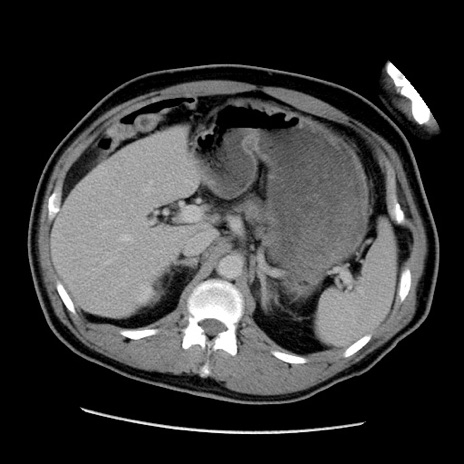

症例22(横断像)

【症例】50歳代男性

【主訴】腹痛

【現病歴】AVMからの被殻出血のため回復期リハ病棟入院中。 本日午後3時頃急に下腹部痛が出現した。

【既往歴】AVM、被殻出血、虫垂炎、高血圧

【身体所見】意識晴明、左半身不全麻痺、会話の理解は良好、36.5°C、腹部:膨隆、全体に板状硬、下腹部正中に圧痛点あり、反跳痛-、筋性防御不明、右下腹部にope scar

【データ】WBC 9400、CRP 0.06